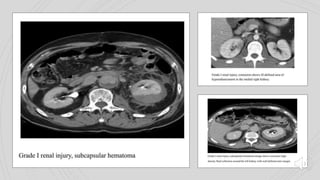

Grade I Grade II Grade III Grade IV Grade V

Contusions and

subcapsular hematoma

are key terms used In

the identification

Contusions appear on

portal venous phase

CT images as globular,

ovoid or round poorly

demarcated area of

relatively poor

enhancement

Subcapsular

hematoma are

confined by renal

capsule. These are non

enhancing cresentric or

lentiform shaped fluid

collections